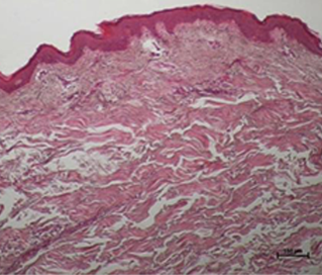

눈으로 직접 확인하는

콜라겐 활성 변화

온다리프팅 시술 후 진피의 콜라겐이 활성화 되고

늘어져 있던 콜라겐이 수축되는 것을 알 수 있습니다.

스킨타이트닝과 리프팅 효과가 동시에 이루어져

만족스러운 피부 리모델링이 이루어집니다.

*진피의 콜라겐(분홍색 영역) 활성화